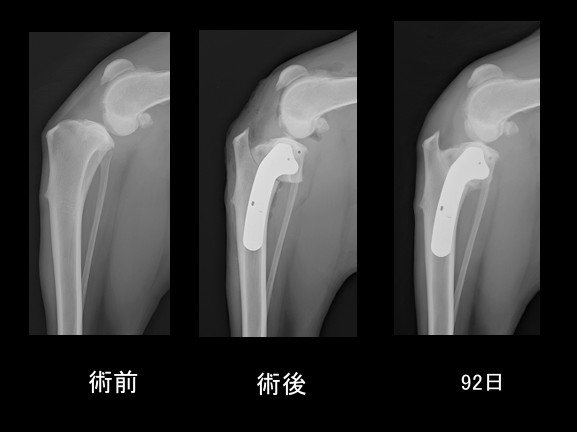

脛骨近位の関節の平らな場所(脛骨高平部)を水平にする手術なので、脛骨高平部水平化骨切り術(Tibial Plateau Leveling Osteotomy :TPLO)と呼ばれ、術後の成績が大変良いため、世界各国で行われるようになっています。

まるちゃんは術後のインプラントの変位も無く、順調に骨癒合し、元のように歩けるようになりました。